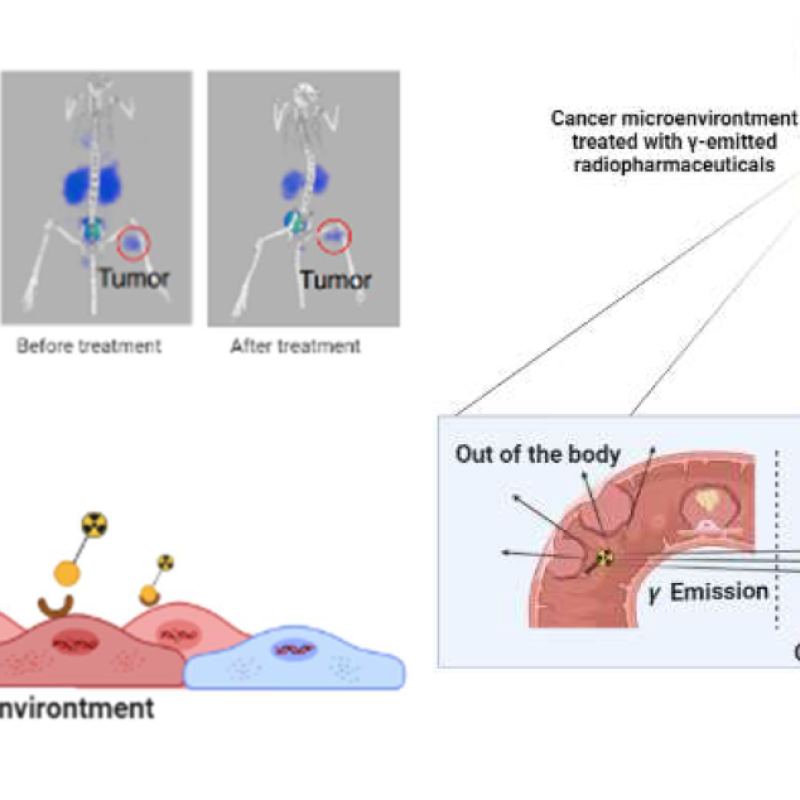

The Chemical Scaffold of Theranostic Radiopharmaceuticals: Radionuclide, Bifunctional Chelator, and Pharmacokinetics Modifying Linker

- Holis Abdul Holik, Faisal Maulana Ibrahim, Angela Alysia Elaine, Bernap Dwi Putra, Arifudin Achmad, and Achmad Hussein Sundawa Kartamihardja

- Molecules (MDPI)

- 10.3390/molecules27103062

- Received: 17 March 2022 / Revised: 27 April 2022 / Accepted: 5 May 2022 / Published: 10 May 2022